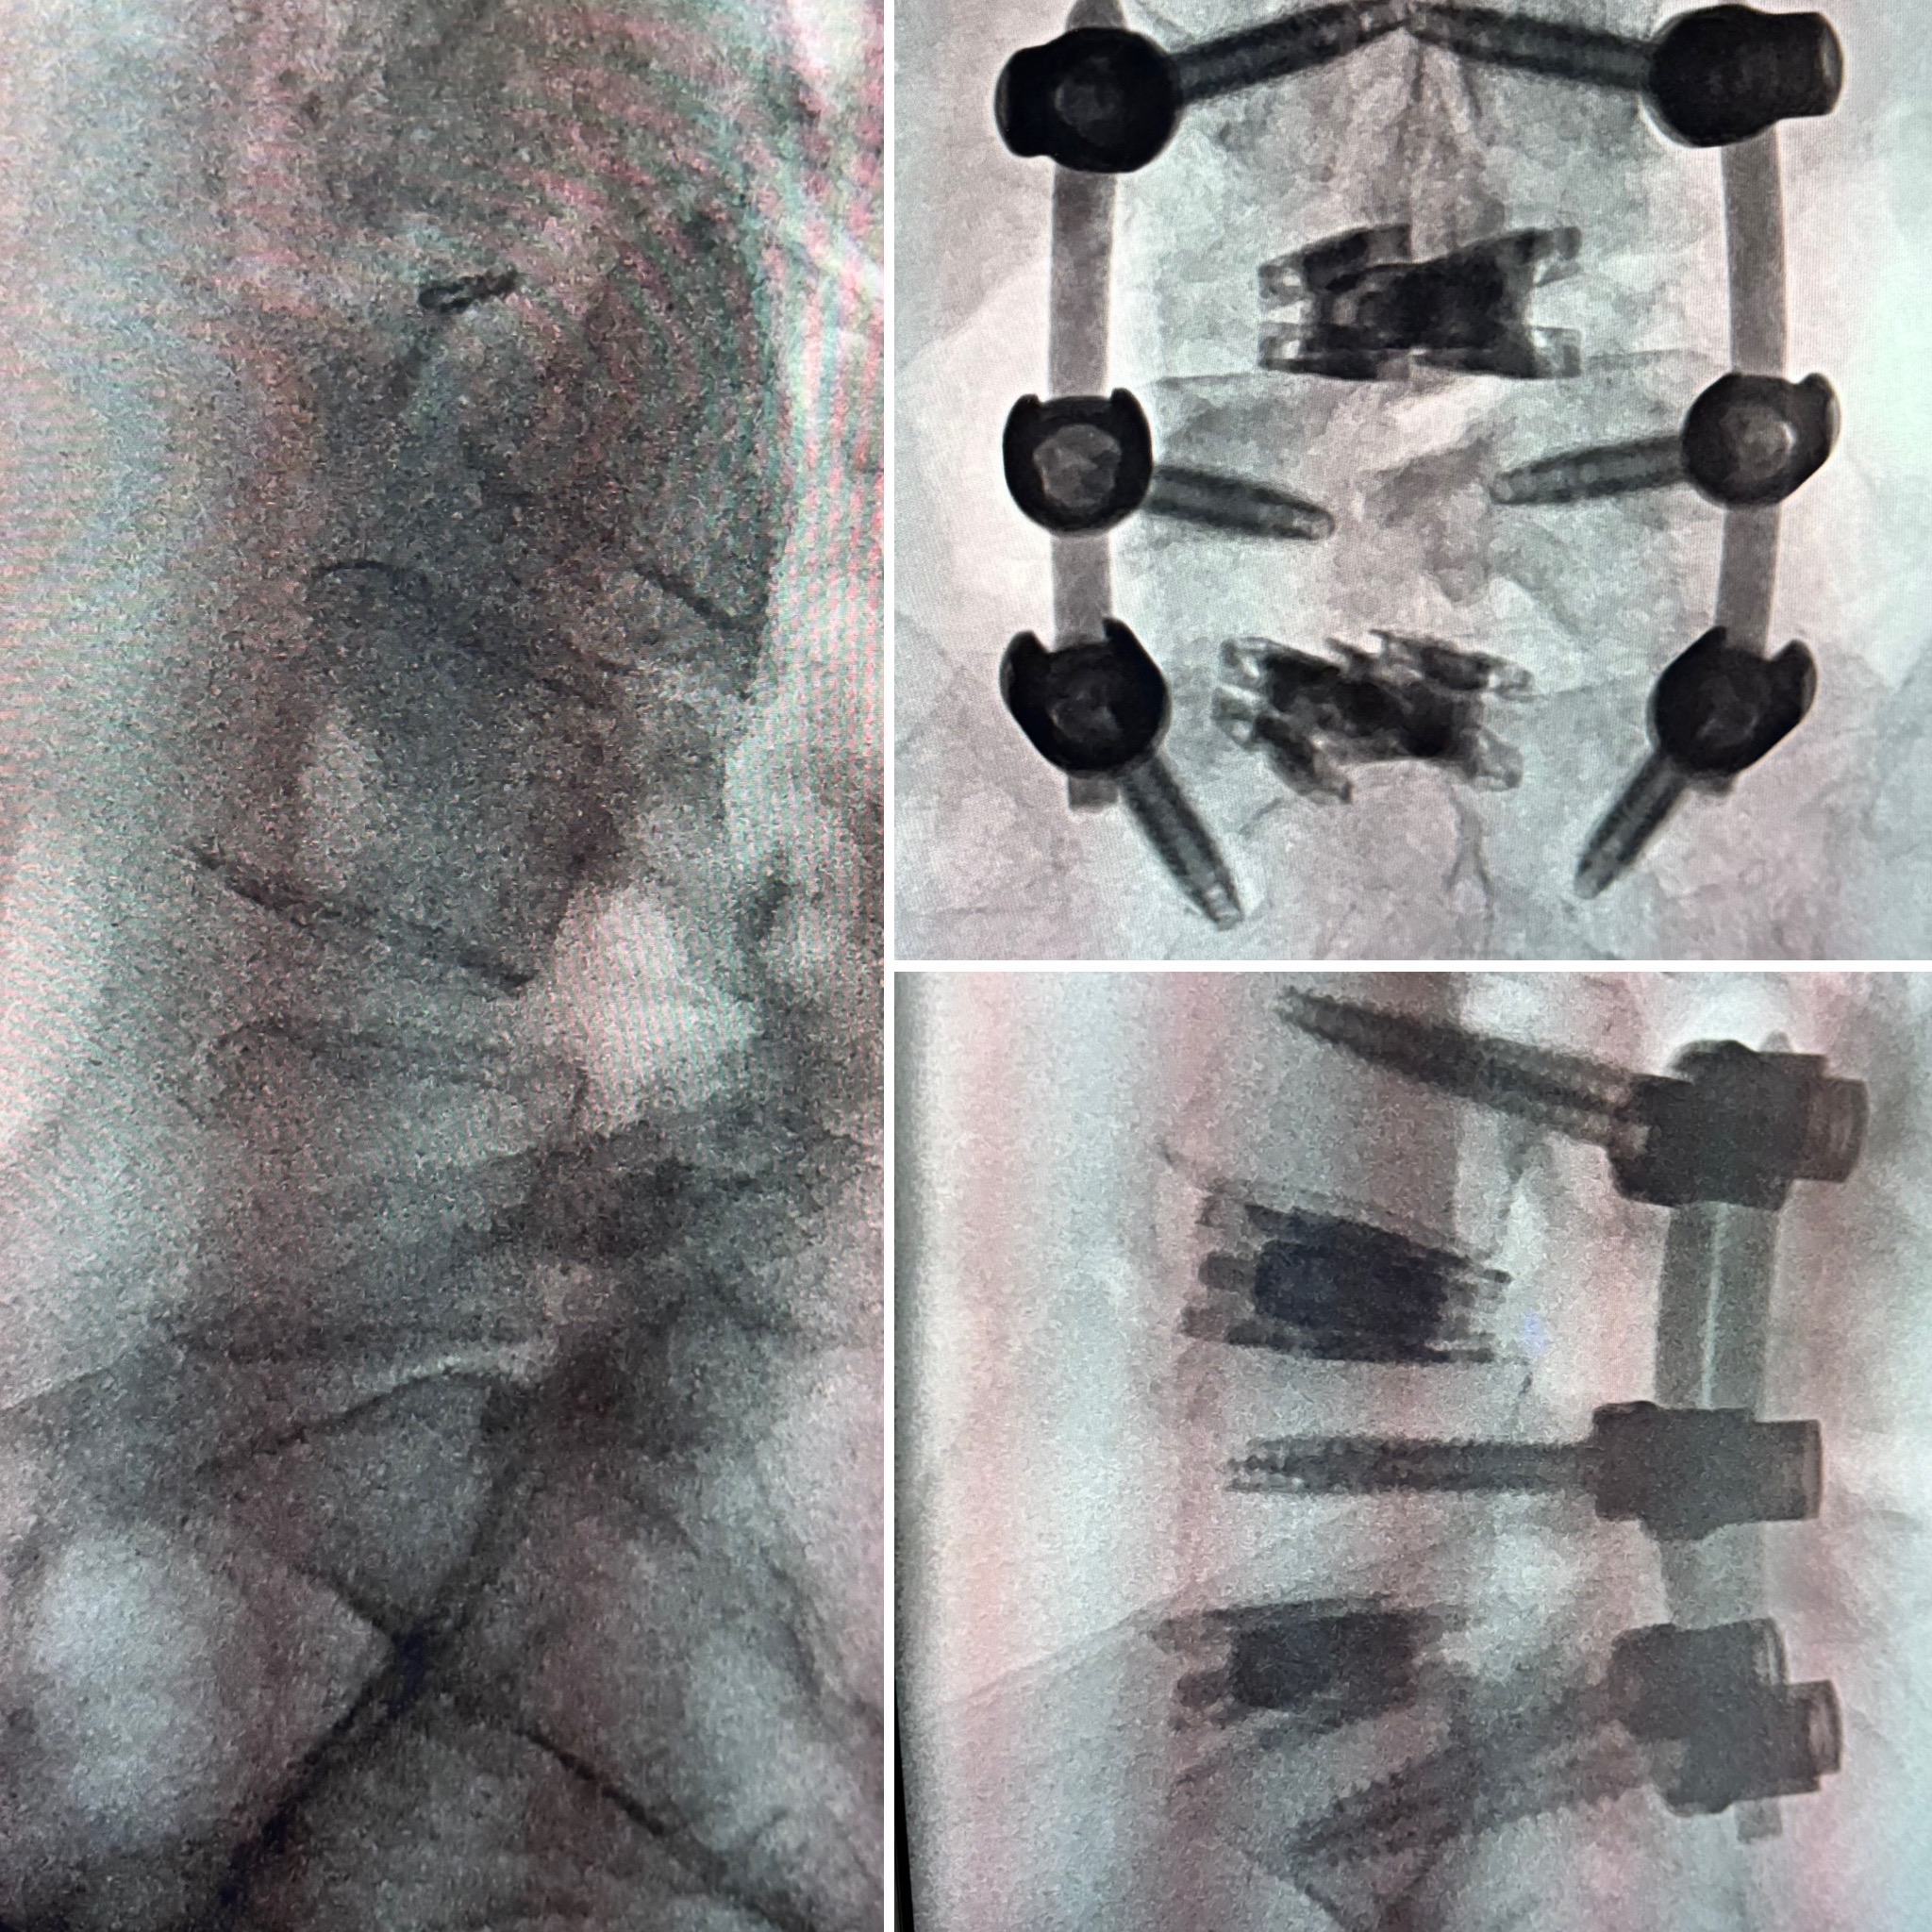

dualX®Slim transforms the fusion environment from insertion to spinal restoration by delivering a powerful dual-expanding implant through a minimally-invasive or endoscopic approaches. dualX®Slim has one of the smallest insertion profiles in the market while still expanding in both horizontal and vertical directions to provide an ALIF-sized final geometry with higher degrees of lordosis (8°, 12°, 15°, 18°*) through the patented trueLordosis™ technology.

Lateral expansion establishes stable footprint Large, center bone graft chamber for post-expansion grafting

20 mm Fully Expanded Width

Powerful vertical expansion restores disc height for decompression

Vertical expansion assists in direct and indirect decompression Multiple lordotic angles restore sagittal balance